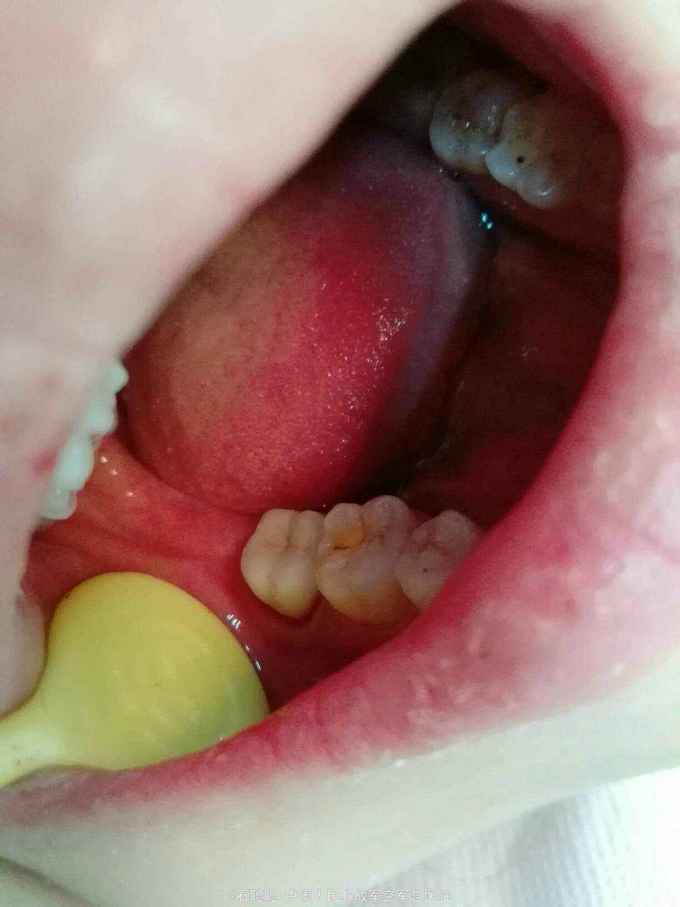

右下7全瓷嵌体冠修复

检查:47合面见白色暂封物完整在位,近中、远中、颊侧、舌侧壁厚度>2mm。咬合紧。叩痛-,无明显松动,牙龈未见明显异常,牙周探诊深度2mm。 根尖片:47根管内高密度充填影像,恰填,牙周膜、根尖区及根分叉未见异常

诊断:47牙体缺损 治疗计划:47全瓷嵌体冠修复 处置:47去除暂封,磷酸锌垫底,光固化覆合树脂充填,预备全瓷嵌体冠,取模,比色3M2,制作临时冠,调合,磨光,粘固 一周后复诊: 检查:临时冠完整在位,无松动,叩痛- 处置:去除47临时冠,试戴全瓷嵌体冠,调合,抛光,U200粘接 医嘱:勿用患牙咀嚼脆骨、坚果等过硬食物 口腔卫生宣教:巴斯刷牙法,牙线使用方法 不适复诊

讨论:这是常一例规的后牙根管治疗后要求修复的病历,患牙的对合略有伸长,咬合紧,尽管将对合做了降合处理,仍会降低龈合距离,削弱全冠的固位力,幸运的是47的四个轴壁均完整并且高度、厚度能满足制作嵌体冠的需要,可以利用髓腔制备固位形,明显改善了固位不足的状态。嵌体预备要点要满足轴壁无倒凹,有2-5度的合方外展,与牙冠就位道一致。